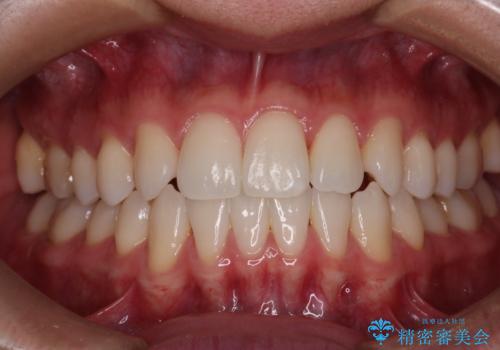

右上2番が欠損しているため、見た目と噛み合わせの両方のバランスを整えるために経過を追いながら必要な部位にゴム掛けをしました。

最終的に、見た目も噛み合わせも患者様に満足いただけました。

また矯正後、患者様の希望で

メタルインレーをセラミックインレーにやりかえさせていただき、さらに綺麗に仕上がりました。